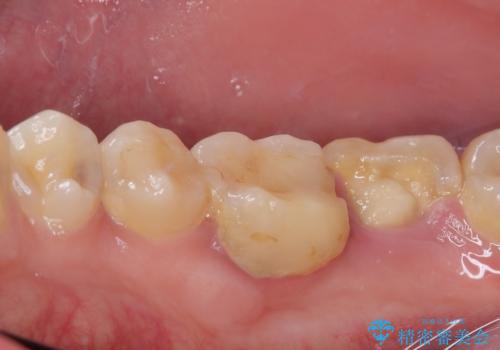

- 右下の奥歯が大きく欠けてしまったのを治したいと来院された患者様です。

舌側の歯冠がなくなってしまっていて、健全な歯質が歯茎の下にある状態です。

このままの状態だと土台がたてられず被せものがいれられないため、歯肉の切除と歯槽骨の形態修正を行い、歯の健全な部分が歯肉の外に出てくるようにしたうえで、オールセラミッククラウンによる補綴治療を行うこととしました。